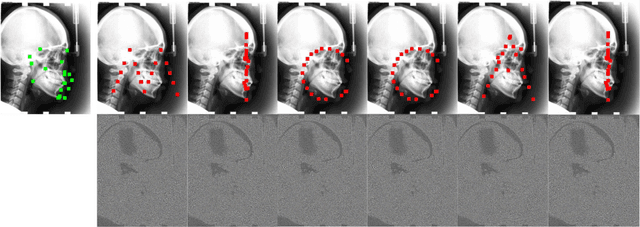

Recent methods in multiple landmark detection based on deep convolutional neural networks (CNNs) reach high accuracy and improve traditional clinical workflow. However, the vulnerability of CNNs to adversarial-example attacks can be easily exploited to break classification and segmentation tasks. This paper is the first to study how fragile a CNN-based model on multiple landmark detection to adversarial perturbations. Specifically, we propose a novel Adaptive Targeted Iterative FGSM (ATI-FGSM) attack against the state-of-the-art models in multiple landmark detection. The attacker can use ATI-FGSM to precisely control the model predictions of arbitrarily selected landmarks, while keeping other stationary landmarks still, by adding imperceptible perturbations to the original image. A comprehensive evaluation on a public dataset for cephalometric landmark detection demonstrates that the adversarial examples generated by ATI-FGSM break the CNN-based network more effectively and efficiently, compared with the original Iterative FGSM attack. Our work reveals serious threats to patients' health. Furthermore, we discuss the limitations of our method and provide potential defense directions, by investigating the coupling effect of nearby landmarks, i.e., a major source of divergence in our experiments. Our source code is available at https://github.com/qsyao/attack_landmark_detection.